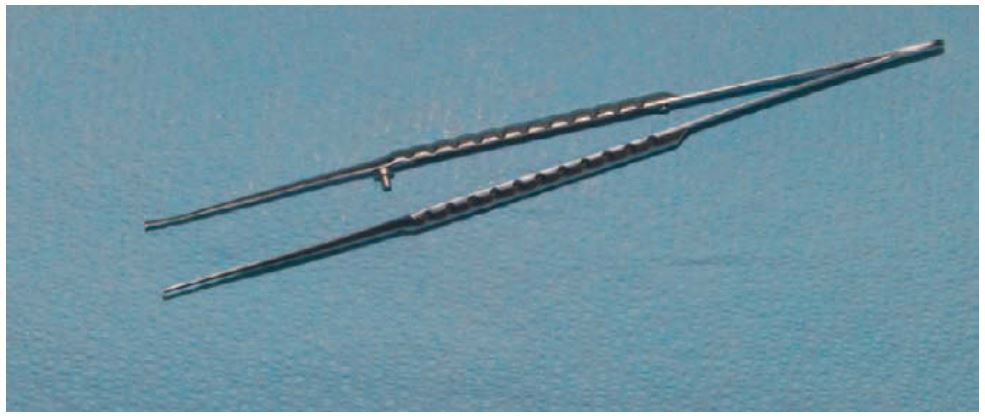

Kẹp phẫu tích (kẹp mô)

Khi thực hiện phẫu thuật trên mô mềm, phẫu thuật viên cần giữ vững 1 bên vạt để xuyên kim qua, hoặc giữ vạt trong khi cắt, khi đó dụng cụ được sử dụng nhiều nhất là kẹp Adson.

Kẹp phẫu tích là dụng cụ thon, mảnh với đầu tác dụng có răng hoặc không có răng. Khi sử dụng phải chú ý không kẹp quá chặt vì sẽ gây tổn thương mô. Kẹp phẫu tích DeBakey cũng tương tự nhưng dài hơn nên dễ đưa vào những vùng mô sâu (H2.16).

Kẹp phẫu tích của Nga thì có đầu tác dụng to, tròn, để kẹp mô nhưng chủ yếu thích hợp khi kẹp các mảnh gãy vỡ, ốc vis hoặc các dụng cụ khác. Ngoài ra còn được sử dụng để kẹp và đặt gạc vào trong miệng.